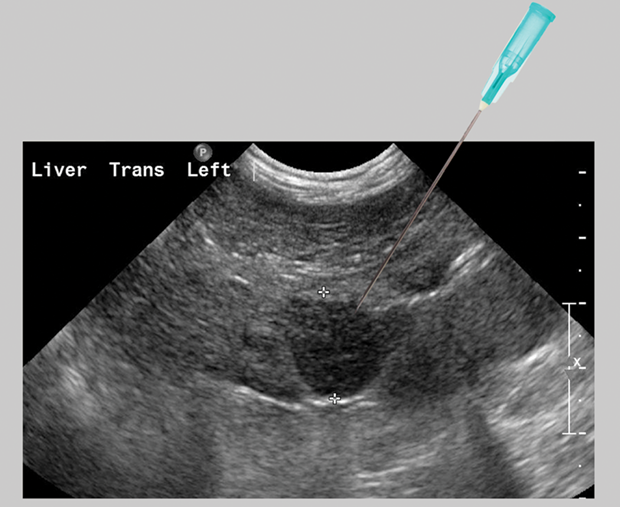

biopsy needle bracket, liver biopsy, gallbladder biopsy, pancreas biopsy Liver Biopsy Fluid Intake After • if you have questions about when to restart any. You may be given pain medicine, such as. Don't soak in a bathtub until the incision is healed. Soreness after a liver biopsy can last for a few days. You should not go out of town for at least 7 days after your biopsy. Don’t lift anything heavier than 10. Liver Biopsy Fluid Intake After.

What to Expect at your UltrasoundGuided Liver Biopsy Procedure Liver Biopsy Fluid Intake After Don’t lift anything heavier than 10 pounds for up to 1 week after the procedure, or as advised by. Eating before liver biopsy — you should have nothing to eat or drink for six hours before the procedure. Soreness after a liver biopsy can last for a few days. Pain at the biopsy site is the most common complication after a. Liver Biopsy Fluid Intake After.